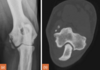

Q

90 day labrador, CT at level of semilunar / trochlear notch. Is this normal or delayed?

A

Should be fused by 10 weeks (70 days), but lit says considered delayed/incomplete if the lucency is visible after 100 days.